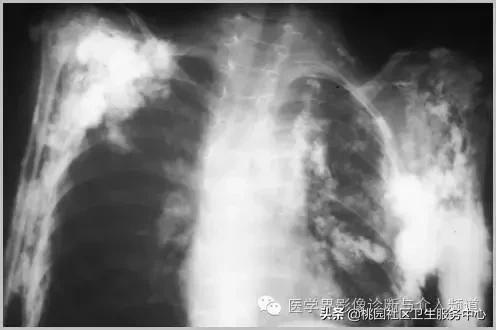

皮肌炎